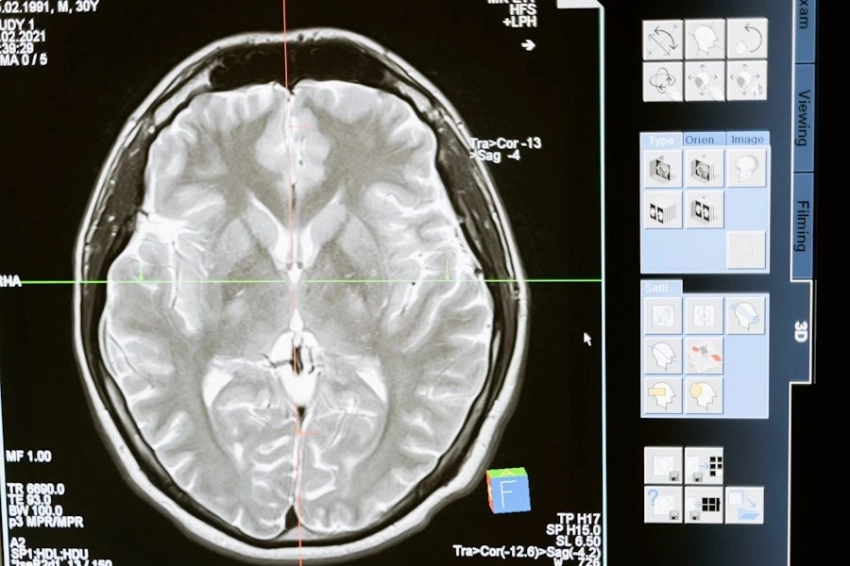

Транскраниальная магнитная стимуляция (TMS) — это метод медицинского исследования и терапии, который использует магнитные поля для воздействия на мозг человека. Этот метод немедленно и неинвазивно воздействует на активность мозга путем создания переменного магнитного поля над кожей головы.

Магнитное поле: устройство TMS создает переменное магнитное поле, которое проникает через кожу и череп, достигая мозга. Это поле воздействует на нейронную активность.

Эффект на нейроны: магнитное поле, приходящее на мозг, способствует изменению потенциалов мембран нейронов, что может оказать влияние на их активность и связи между нейронами.

Транскраниальная магнитная стимуляция используется в медицинских исследованиях для изучения функций мозга и их связи с различными психическими и нейрологическими состояниями, а так же для лечения некоторых болезней. Этот метод может помочь в восстановлении или модуляции активности мозга у пациентов с различными патологиями.